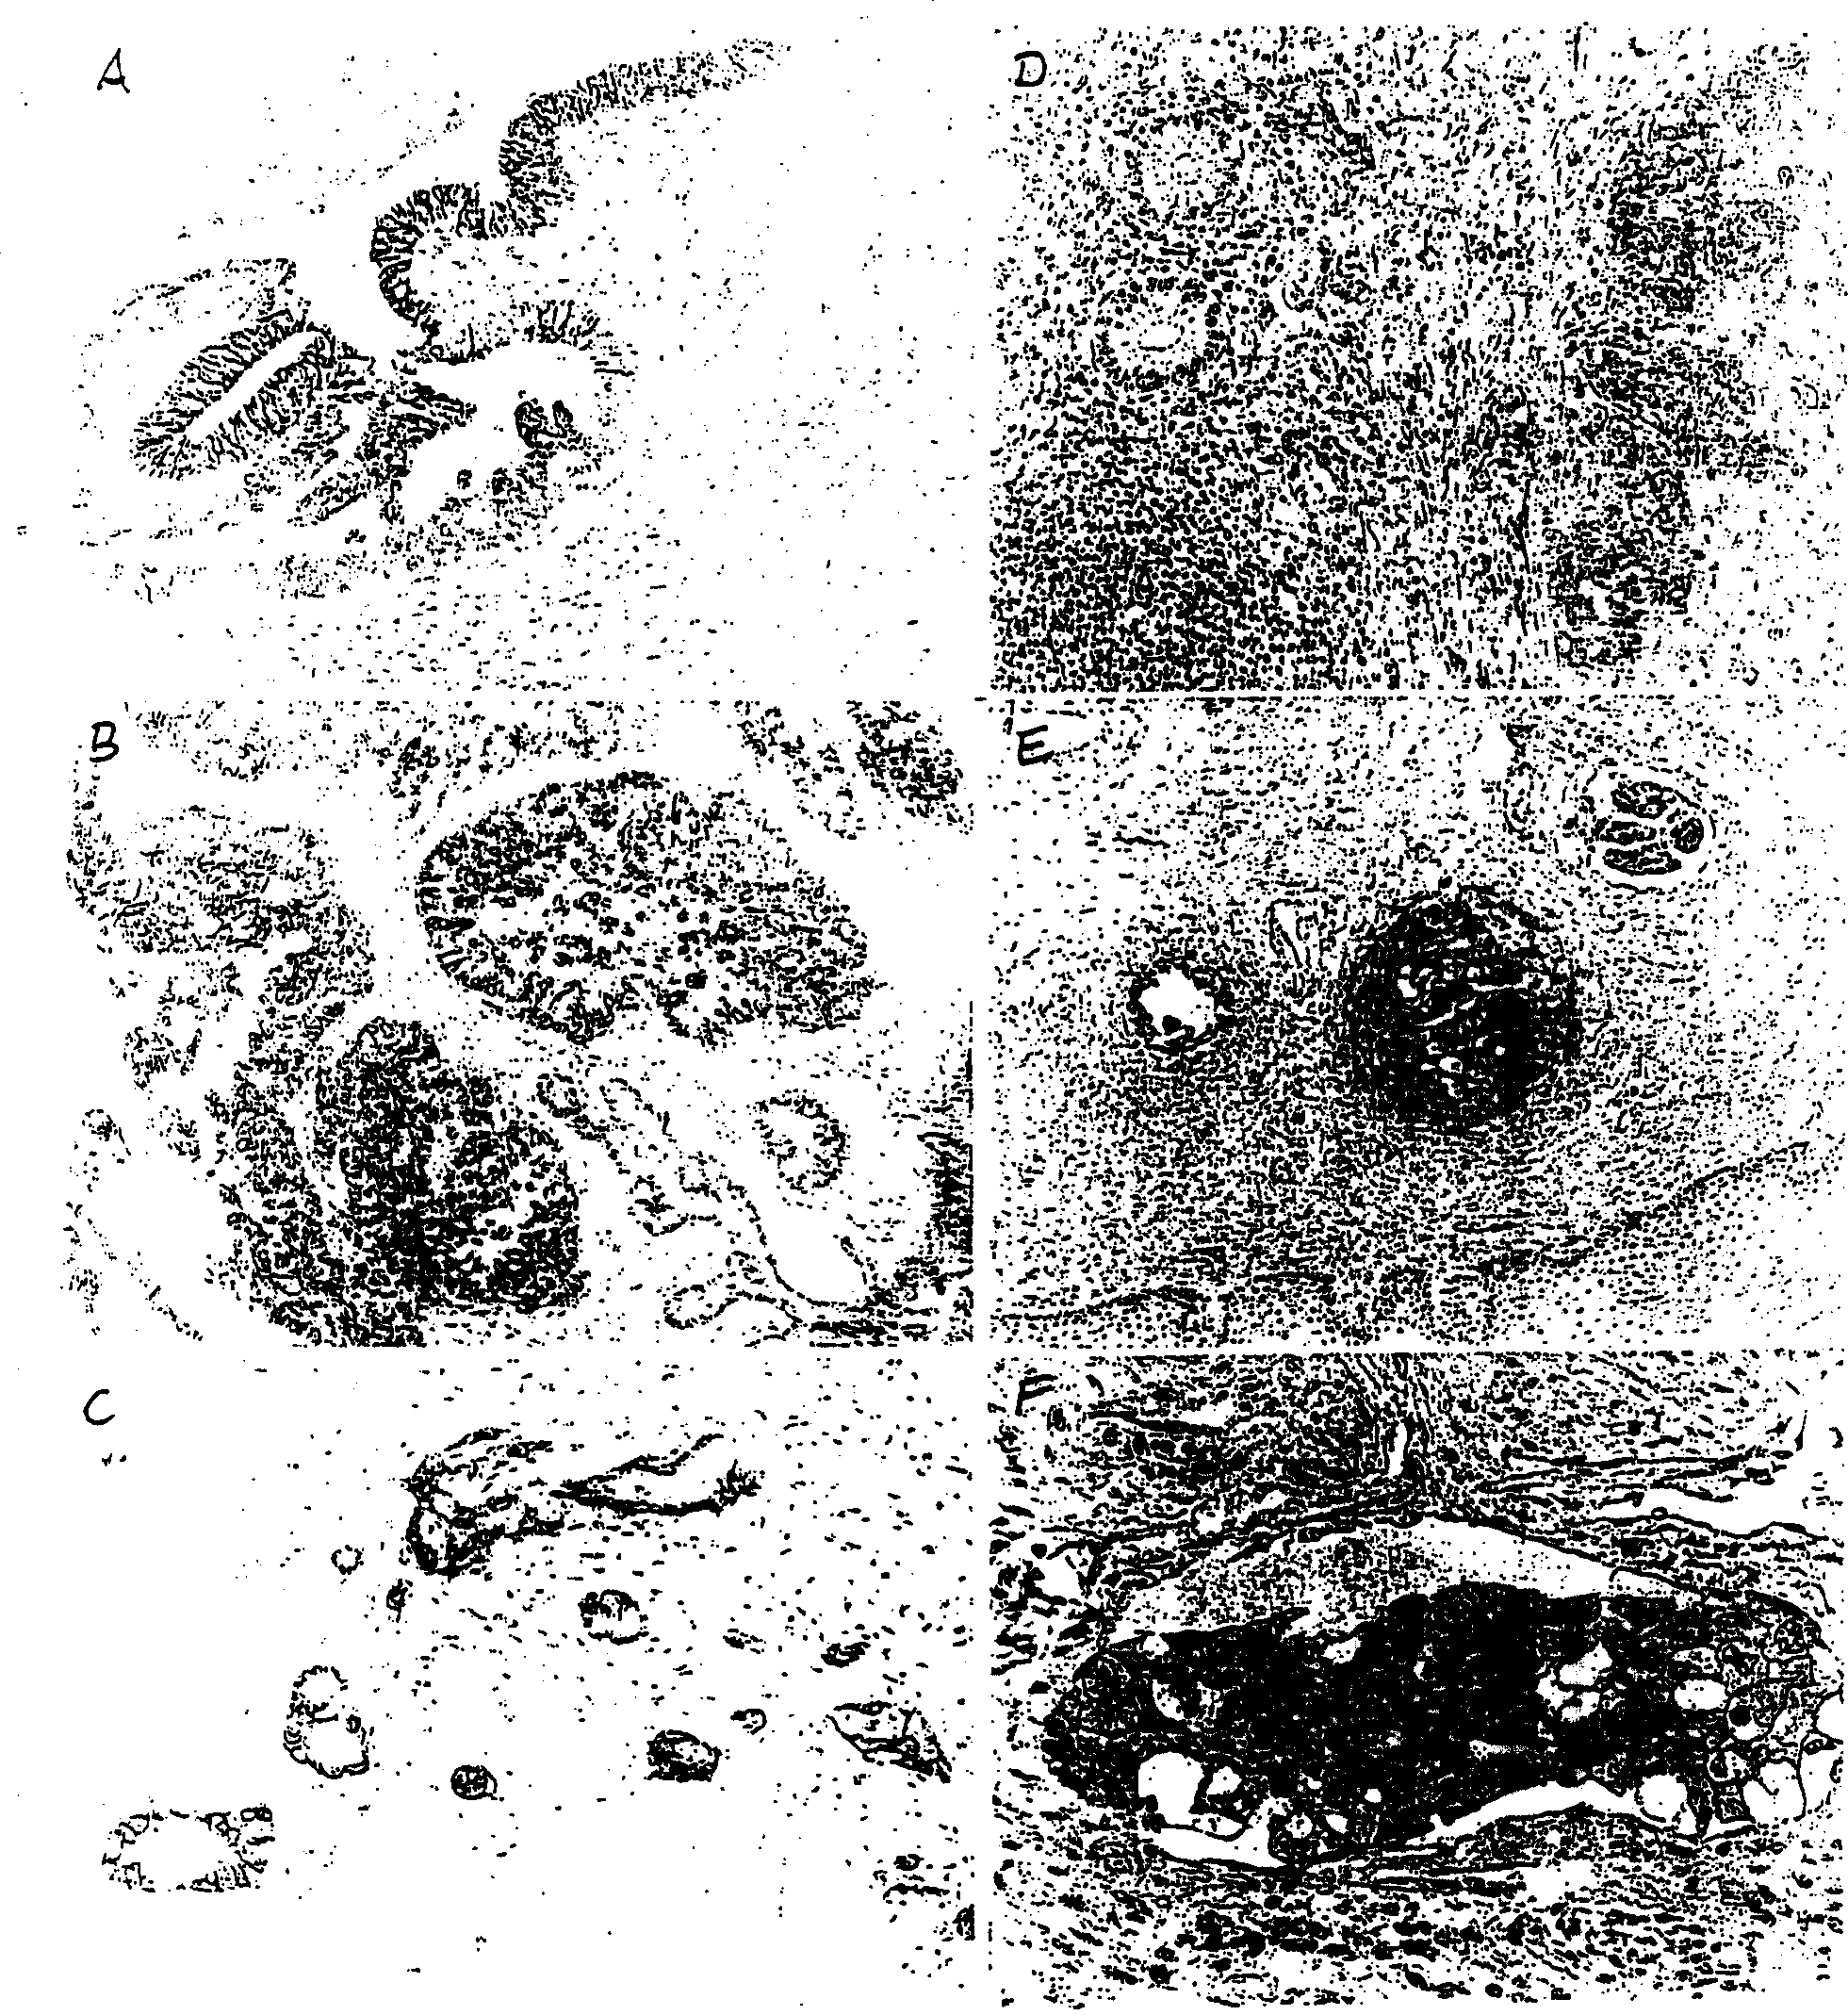

基于L1粘附分子的卵巢和子宫内膜肿瘤的诊断和治疗方法